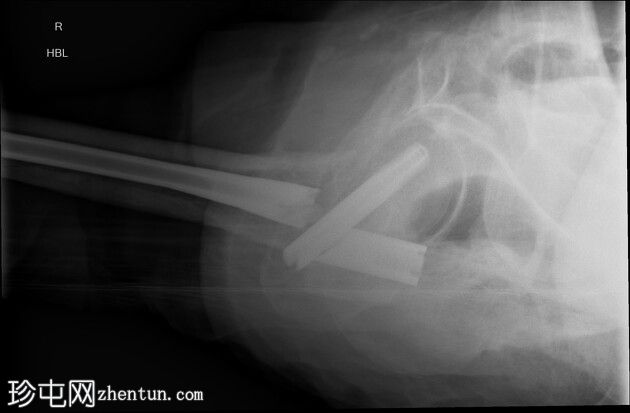

右侧髓内钉近端骨折(位于拉力螺钉孔位)。

空心髋螺钉组件完好。

股骨转子间骨折延伸至股骨近端转移灶,小转子粉碎。

在本例中,髓内钉断裂发生在拉力螺钉孔(穿过股骨颈的螺钉)的水平,该水平可能是髓内钉本身较薄弱的部位。靠近该水平的溶骨性病变可能导致了不稳定性和髓内钉的异常应力。